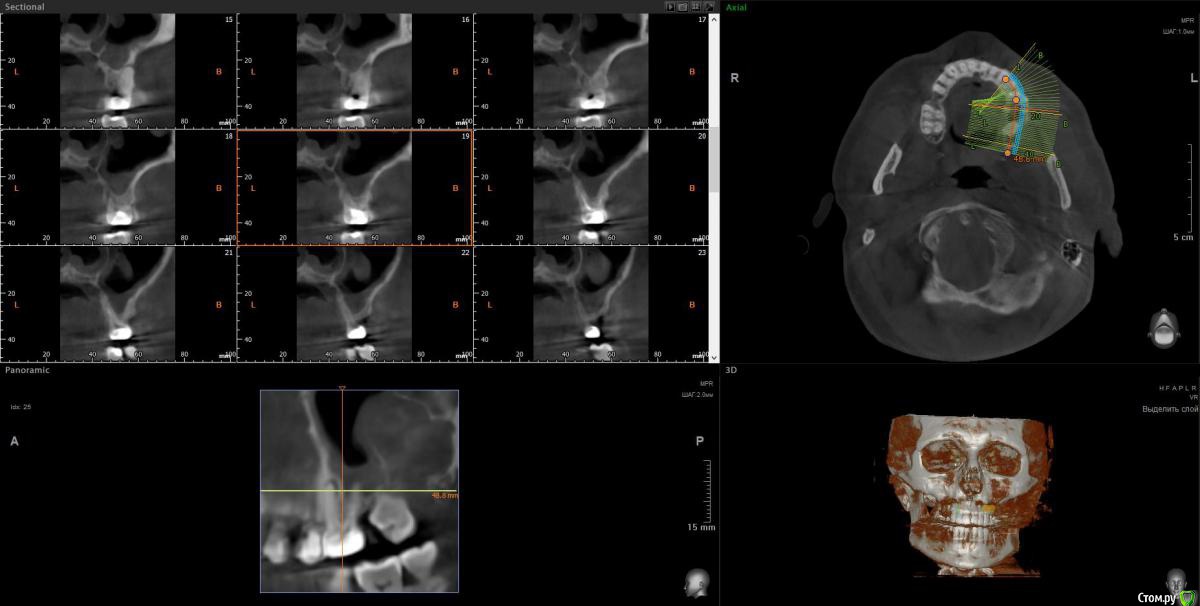

wladdX Опубликовано 5 марта, 2019 Поделиться Опубликовано 5 марта, 2019 Корональная проекция Сагиттальная справа Сагиттальная слева 16 26 28 Ссылка на комментарий

kramer Опубликовано 5 марта, 2019 Поделиться Опубликовано 5 марта, 2019 В общем скачал я КТ. Что касается зуба 26, да, там есть признаки воспаления вокруг корней, лечить / удалять зависит от состояния тканей зуба и возможностей врача. Но лично мне не кажется, что этот зуб играет главную роль в возникшем гайморите. Обратите внимание, в области 8 зуба (см. срез) внутри пазухи есть некий очаг, содержащий неоднородные по плотности элементы (более светлые включения, а выше пузырьки воздуха). Снимок не особо четкий, но такое ощущение, что в области 8 зуба вообще нарушена целостность боковой стенки пазухи. Кроме того, с правой стороны все зубы в порядке, а явления гайморита тоже имеются (там вообще почти вся пазуха забита). Соустья с носом закрыты. В общем, в данной ситуации я бы более детально обследовал 8 зуб, если там все нормально, то пусть ЛОРы эндоскопически лезут в пазухи и убирают это все. Ссылка на комментарий